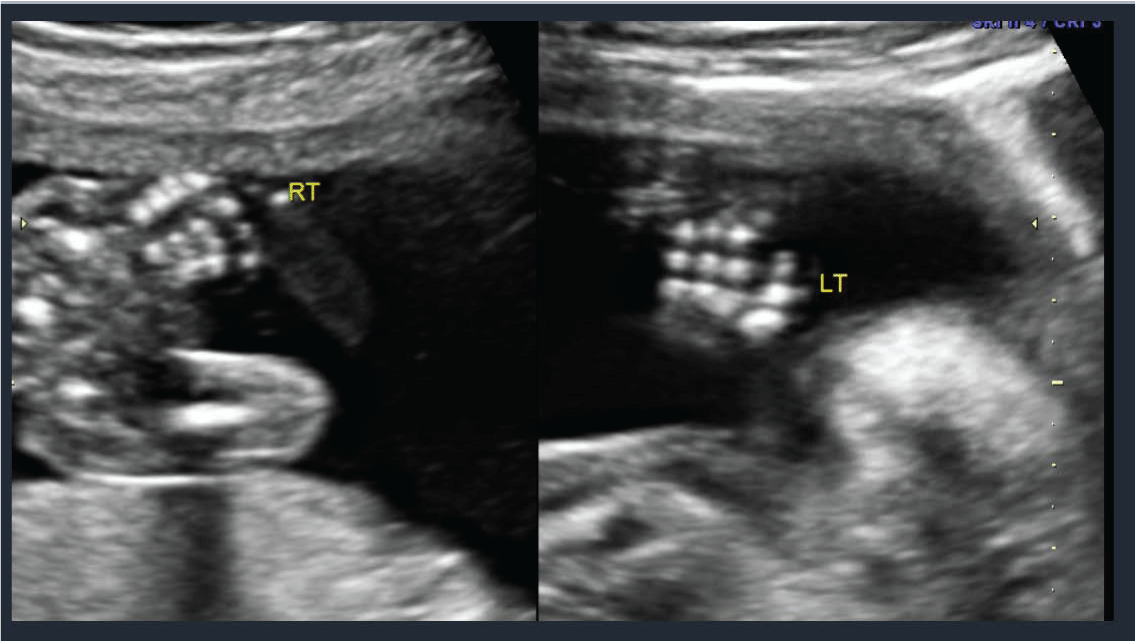

A 22 year old prima gravida patient received a viability ultrasound in the Obstetrics and Gynecology Department at 13 weeks 4 days to test for any obvious phenotypic abnormalities. Simultaneously she declined any aneuploidy screening. Subsequently she was completed regular prenatal visits in the antenatal care clinic. She had her next ultrasound at 19 weeks 4 days at which time she also had a mid-trimester anatomy scan. The viable intrauterine pregnancy was noted to be accompanied by a unilateral choroid plexus cyst (Figure 1) along with dextroposition of the heart (Figure 2). The fetal heart was in the right hemithorax without discrete mass lesions in the left hemithorax while the stomach was appropriately positioned in the left upper quadrant and the diaphragm appeared intact. No complex cardiac defects or other structural malformations were identified (Figure 3 and Figure 4). Estimated fetal weight was appropriate for gestational age (Figure 5). These findings were discussed and all prenatal testing options were reviewed with the patient and her spouse. At 20 weeks 4 days a repeated ultrasound showed isolated dextroposition of the heart with the choroid plexus cyst no longer being evident. At that time the patient requested and completed amniocentesis. Amniotic fluid alpha fetoprotein levels were also normal. Initial cytogenetic analysis for common chromosome aneuploidy revealed a normal male pattern for chromosomes 13, 18, 21, X and Y by fluorescence in situ hybridization (FISH). However, the chromosomal microarray analysis (CMA) suggested mosaic Trisomy 18. An abbreviated karyotype subsequently confirmed three copies of chromosome 18 in three out of four metaphase cells confirming 47,XY,+18/46,XY mosaicism. The patient elected to terminate the pregnancy based upon these results, Dilation and evacuation (D&E) was completed at 22 weeks and 4 days. The autopsy revealed: Normal heart in shape and size. Left pulmonary artery, aortic trunk with valve and atrial septum are disrupted. The right pulmonary artery is intact and normal. The left atrial appendages are normal in shape and consistent with normal isomerism. The mitral, pulmonic and tricuspid valves are normal. There is no ventricular septal defect. Heart anomalies are not identified. However, the examination was suboptimal due to fetal disruption secondary to the (D&E) procedure.